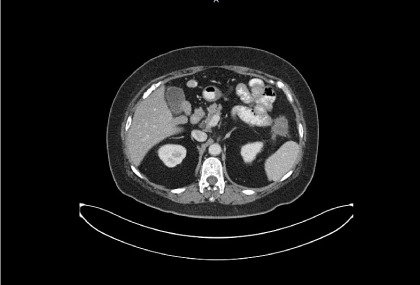

After failure of multiple lines of chemotherapy and biologics, the patient was started to receive 160 mg/day of regorafenib from 2015-10-13, then decrease to 120 mg/day and eventually to 80 mg/day because of elevated liver enzyme. CT scan on 2015-12-23 was reported as “a 3x3.6cm growing metastatic mass with central necrosis in left upper abdomen with adjacent small bowel invasion” (Figure 1).

Figure 1. A 4x3.5 cm necrotic omtenal nodule in left upper abdomen, with increasing size of the mental nodular lesion comparing to previous CT study